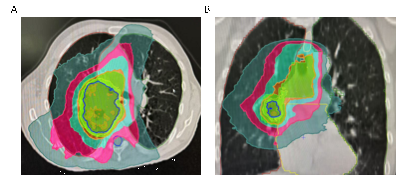

靶区勾画与放疗物理计划制定是精准放疗最为核心的步骤,该环节不需要患者的参与,但是需要患者的理解和配合。第一:放疗靶区勾画和物理计划制作非常复杂,需要反复优化,以达到最佳效果。放疗计划完成后,后续放疗没有特殊将完全按照该计划执行。所以该步骤需要一定的时间,需要病人耐心等待。第二:如图2所示,在照射肿瘤的同时(蓝线包绕区域),我们正常的肺组织、心脏、食管正常器官不可避免会受到一定的低剂量照射。这一点需要患者理解,最重要的是在治疗过程中,密切关注有无这些正常器官放射损伤相关症状。若有不适可以及时告知主管医生进行早期干预。

图2:肺癌放疗计划剂量分布图